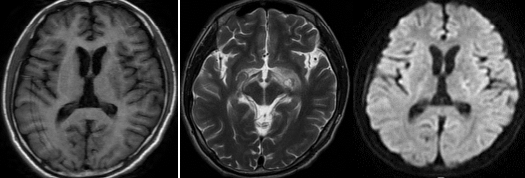

61岁男患,癫痫。2014年头MRI如下:

2020年头MRI如下:

答案:脑淀粉样血管病相关炎症(CAA-RI)。多呈急性或亚急性起病,最常见的表现是认知及行为改变,可表现为不同程度的痴呆、幻觉、人格改变、意识障碍甚至昏迷,其次是偏瘫、偏身感觉障碍、失语、共济失调等局灶性神经功能受损表现。另外,以癫痫、头痛等症状起病的患者亦不在少数,而相比单纯CAA而言,颅内出血的发生率则较低。MRI上最常见的表现为软脑膜明显强化及T2WI或FLAIR上的皮质下白质高信号灶,病灶常为非对称性,可散在分布或融合成片,灰质较少累及。